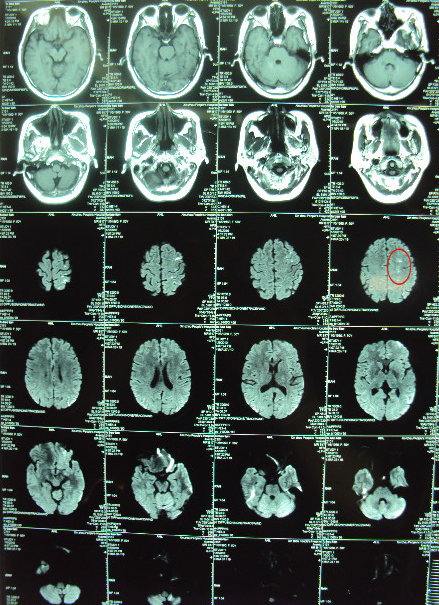

CT显示可见之前的梗塞灶